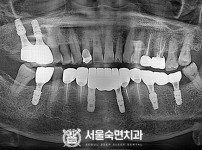

임플란트-전후사진3

치과를-선택할-때-꼭-확인하세요-서울숙면치과-임플란트-전후사진